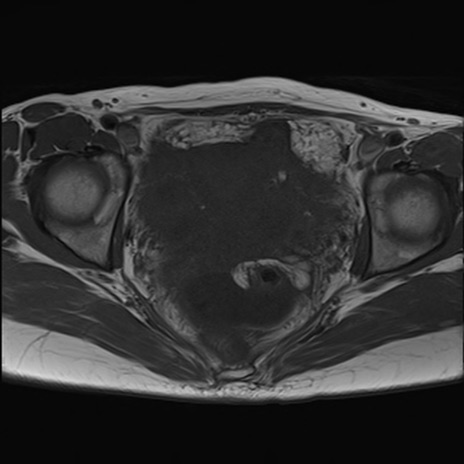

症例39 T1WI(横断像)

MRI(4日後)